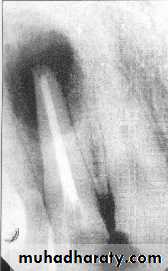

4- Mandibular Incisors: If we take an x-ray from buccal direction we

will find small, tiny root canal, but if we take an x-ray film frommesial or distal direction, we will find large, wide pulp “labiolingually”

with a possibility of two canals one labially and the second

one is located lingually, so we have to widen the root canal orifice

“Labiolingually”.

Also, in the lower incisor, some times we have slight curvature in the

root apex “to the lingual side” so, there is a possibility of perforation

during instrumentation.